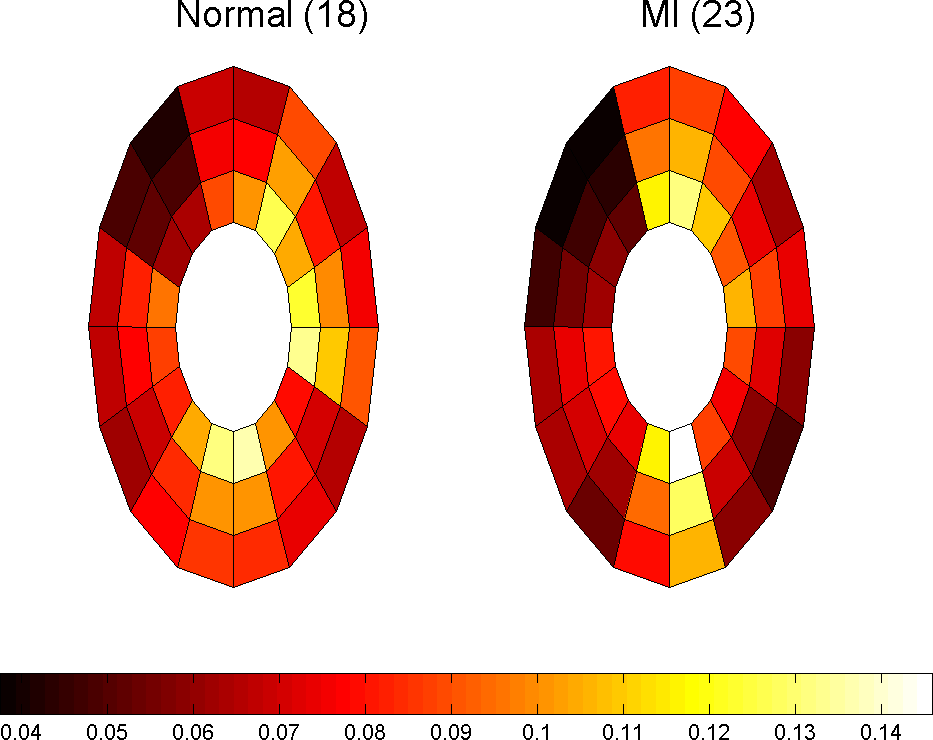

which in 2D case can be simplified because . Using this parameter we are able to monitor the changes in strain maps of heart muscle during deformation. Computing effective strain values for different slices of cardiac muscle, these values are used for comparison between healthy and MI subjects. Fig. 10 represent the results for first slice of healthy subjects, 18 and 25, and MI subject 23 during the cardiac cycle.

Fig. 11 shows the approximate infarct localization for the MI subject based on the comparison between normal and MI subjects’ effective strain during the cardiac cycle. Since the circulatory system of heart is determined very well, it is possible to make reliable conclusions about the problem that caused MI based on expert diagnosis and using these comparisons.